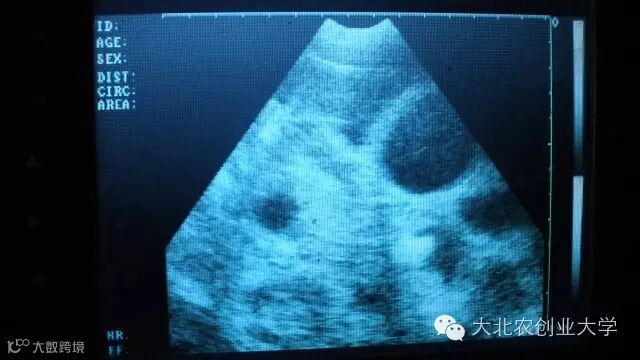

B超检测图片讲解

妊娠38天图像